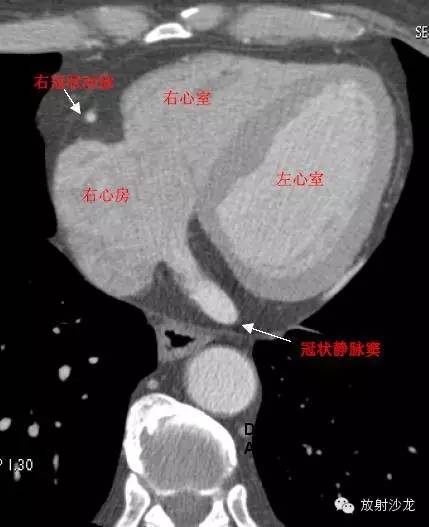

RA -Right Atrium右心房

LV -Left Ventricle左心室

RV -Right Ventricle右心室

RAA –Right AtrialAppendage右心耳

CS -Coronary Sinus冠状窦